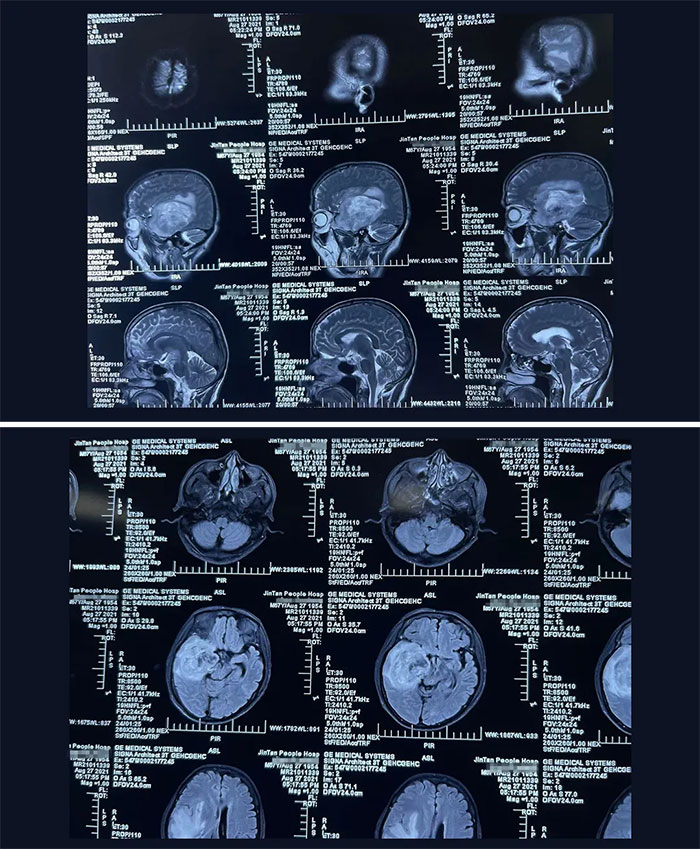

家住江苏省某市的林先生(化名)今年68岁,从事业单位退休下来已经八年了。今年7月,林先生被车撞了一下,当时感到持续性头痛,伴左侧肢体乏力持续加重,在家人陪同下前往当地医院就医。因为平时每年单位都会组织退休员工进行体检,除了头部不做CT及核磁共振MRI外,其他身体部位都体检到的,除头部外身体各处无恙。现在这一查头部,着实让他及家人吓了一大跳。林先生右侧丘脑、基底节、颞叶占位病变,占位体积巨大,最大直径约 8cm,呈浸润性生长、边界不清,周围大片水肿带;脑干、右侧侧脑室受压变形,中线结构受压向左偏移11mm。考虑为脑恶性肿瘤,胶质瘤可能性大。

▲ 丘脑占位病变体积巨大,且与脑组织边界不清,压迫脑干、大脑脚,若任其发展或危及生命

根据患者的病史、症状以及体征,再结合CT和磁共振(MRI)检查,对病变部位以及恶性程度级别,有了初步的临床判断。“患者的脑肿瘤体积巨大,且位于脑部重要功能区,已压迫脑干,颅内高压所致神经功能损害症状明显,随着病情加重,脑组织受压位移程度更为严重,随时可出现脑疝,需立即手术。”教授解释道,脑疝是一种十分凶险的临床危重症,发生速度快,极短时间内就可能造成患者生命危险,病死率、致残率极高,且预后不良。